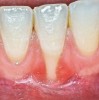

The workshop's group on periodontal soft-tissue root coverage procedures evaluated the predictability of root coverage procedures for single- and multiple-tooth Miller Class I and II10 periodontal recession defects. The workshop concluded that predictable root coverage was possible for Miller Class I and II recession involving a single tooth. When compared with the use of acellular dermal matrix graft (ADMG) (donor tissue) or EMD (porcine origin), procedures using a subepithelial connective tissue graft (SCTG) harvested from the patient's palate provided the best root coverage outcomes in conjunction with a coronally advanced flap.11 As alternatives to autogenous donor tissue, the workshop found strong evidence to support the use of an ADMG or EMD in conjunction with a coronally advanced flap and limited evidence to support the use of platelet-derived growth factor and xenogeneic collagen matrix.11 In addition, root coverage procedures were found to be effective for Miller Class I and II recession defects affecting multiple teeth, although the evidence is limited.11 Figure 1 and Figure 2 show the pretreatment and 1-year postoperative views of a soft-tissue root coverage treatment with SCTG and EMD that used a coronally advanced flap and a tunneling procedure. Figure 3 and Figure 4 depict the pretreatment and 3-year postoperative views of a root coverage procedure with ADMG and EMD that used a coronally advanced flap and a tunneling procedure (this patient was noncompliant following surgery and did not return to the office until the 3-year postoperative appointment).

(1.) Pretreatment view of single incisor with gingival recession exposing the root.

Figure 1